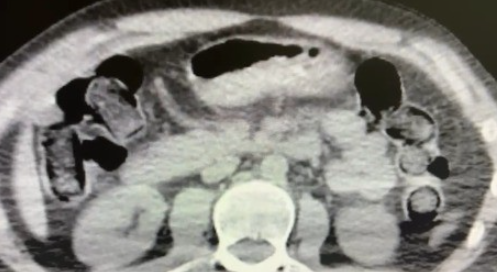

Nevşehir İl Emniyet Müdürlüğü Narkotik Suçlarla Mücadele Şube Müdürlüğü ekipleri, kentte uyuşturucu ve uyarıcı madde ticareti yapmak ve kullanmak suretiyle vatandaşları zehirleyen sokak satıcılarına yönelik çalışma başlattı. Cumhuriyet Başsavcılığı koordinesinde çalışmalarını yoğunlaştıran ekipler, şüpheliler S.B. ve O.R.'nin 'yutma yöntemi' ile kente uyuşturucu madde sevk edeceği bilgisi üzerine operasyon düzenledi. Şüphelilerin ikametlerinde ve araçlarında yapılan aramada 101 kapsül halinde 722 gram uyuşturucu madde, 1 adet hassas terazi, uyuşturucu madde sevkiyatında yutma yönteminde kullanılan muhtelif materyaller, uyuşturucu madde ticaretinden elde edilen 20 bin 210 TL, bin 320 euro ve 10 ABD doları ele geçirildi. Emniyetteki işlemlerinin ardından adliyeye sevk edilen 2 şüpheli, çıkarıldıkları mahkemece tutuklanarak cezaevine gönderildi.